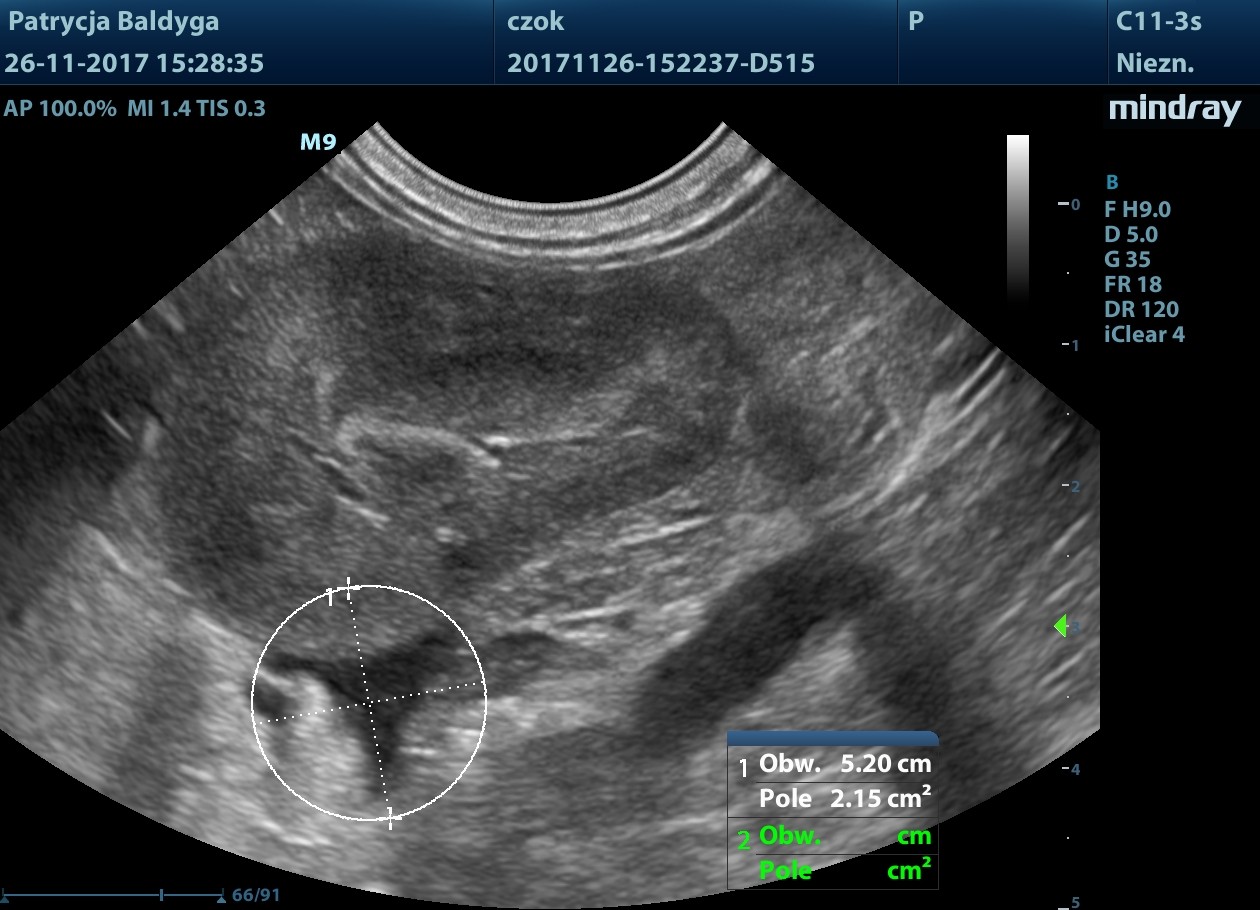

Obecność znacznie zwiększonych ilości wolnego, nieco zagęszczonego płynu w jamie otrzewnej, widocznego w dużej ilości przypęcherzowo, przywątrobowo, pomiędzy pętlami jelit oraz śladowo również w przestrzeni zaotrzewnowej

- co nasuwa duże podejrzenie krwotoku masywnego, najpewniej z wątroby, wskazanie do laparotomii zwiadowczej.